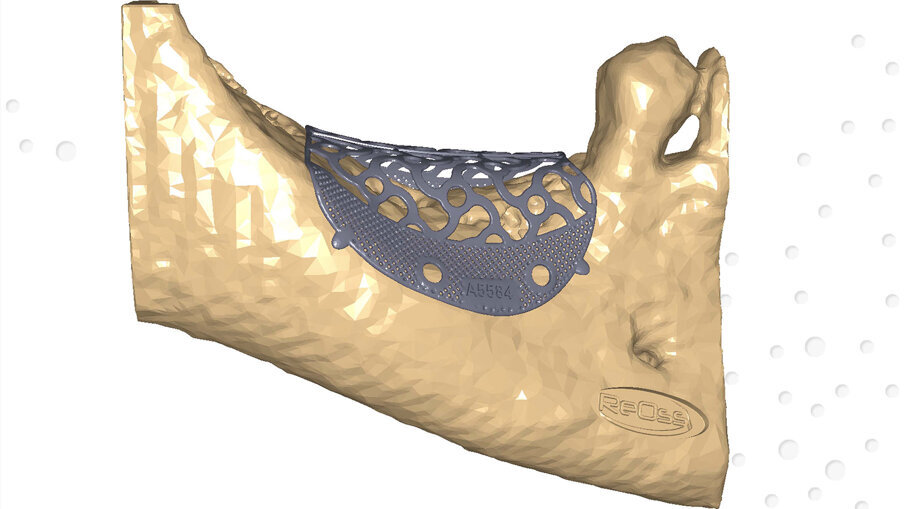

I file Dicom ottenuti, inviati all’azienda produttrice, hanno permesso di ricavare modelli tridimensionali che riproducessero in modo fedele il deficit osseo e sui quali è stata costruita virtualmente e digitalmente la griglia che, dopo approvazione, è stata prodotta. Le dimensioni mesio-distali della griglia erano di 19 mm e l’entità volumetrica del deficit osseo di 1,26 cm3 (Figg. 2a, 2b). Il piano di trattamento ha previsto un intervento di ricostruzione ossea del difetto mediante una griglia customizzata e il contestuale inserimento di 2 impianti endossei e la successiva riabilitazione protesica fissa implanto-supportata.

Figg. 2a, 2b_Modello digitale con il progetto definitivo della griglia in titanio customizzata Yxoss CBR protect.